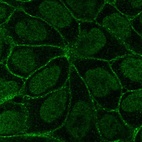

Learn how we validate our antibodies, how we secure their reproducibility, and why we apply enhanced validation. Our antibodies are validated in IHC, ICC-IF, and WB.